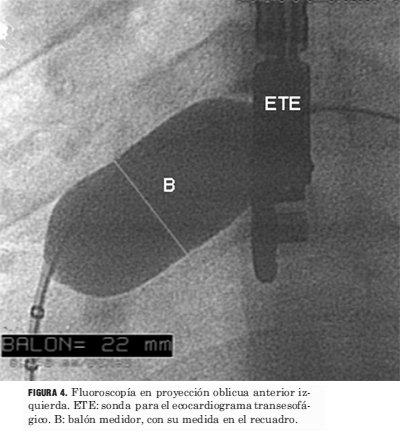

Todos los procedimientos se realizaron bajo anestesia general. En todos los casos se utilizó la vía venosa femoral. Se realizó la medida de la presión arterial pulmonar y cálculo de relación QP/QS (flujo pulmonar/flujo sistémico) mediante oximetrías. Se efectuó angiografía de vena pulmonar superior derecha en oblicua anterior izquierda con la finalidad de determinar las características anatómicas de la CIA y del séptum interauricular (figura 3). Posteriormente se efectuó la insuflación de un catéter balón medidor, con medio de contraste diluido (figura 4), posicionado a nivel del defecto interatrial hasta que cesa el flujo a su través, valorado por el Doppler color en el ETE (figura 5). Ello permite realizar la medida del diámetro de la CIA y elegir el diámetro del dispositivo. Los dispositivos utilizados fueron en tres casos el Cardioseal y en 72 el Amplatzer ASO. Todos los procedimientos fueron realizados con ETE simultáneo con el que se verificó la correcta ubicación del dispositivo antes y después de su liberación, y se descartó el compromiso de estructuras vecinas (figuras 6 y 7).

Figura 4. Fluoroscopía en proyección oblicua anterior izquierda. ETE: sonda para el ecocardiograma transesofágico. B: balón medidor, con su medida en el recuadro.